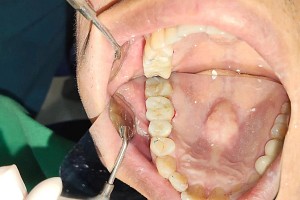

Kết quả sau điều trị

Sau khi hoàn tất gắn răng sứ trên Implant:

- Răng được phục hồi vững chắc, chắc khỏe như răng thật

- Khả năng ăn nhai cải thiện rõ rệt, không còn cảm giác cộm hay khó chịu

- Khớp cắn ổn định, không ảnh hưởng đến các răng xung quanh

- Đảm bảo tính thẩm mỹ tự nhiên, khó phân biệt với răng thật

Anh Quang có thể sinh hoạt, ăn uống bình thường và hoàn toàn yên tâm với kết quả điều trị lâu dài.